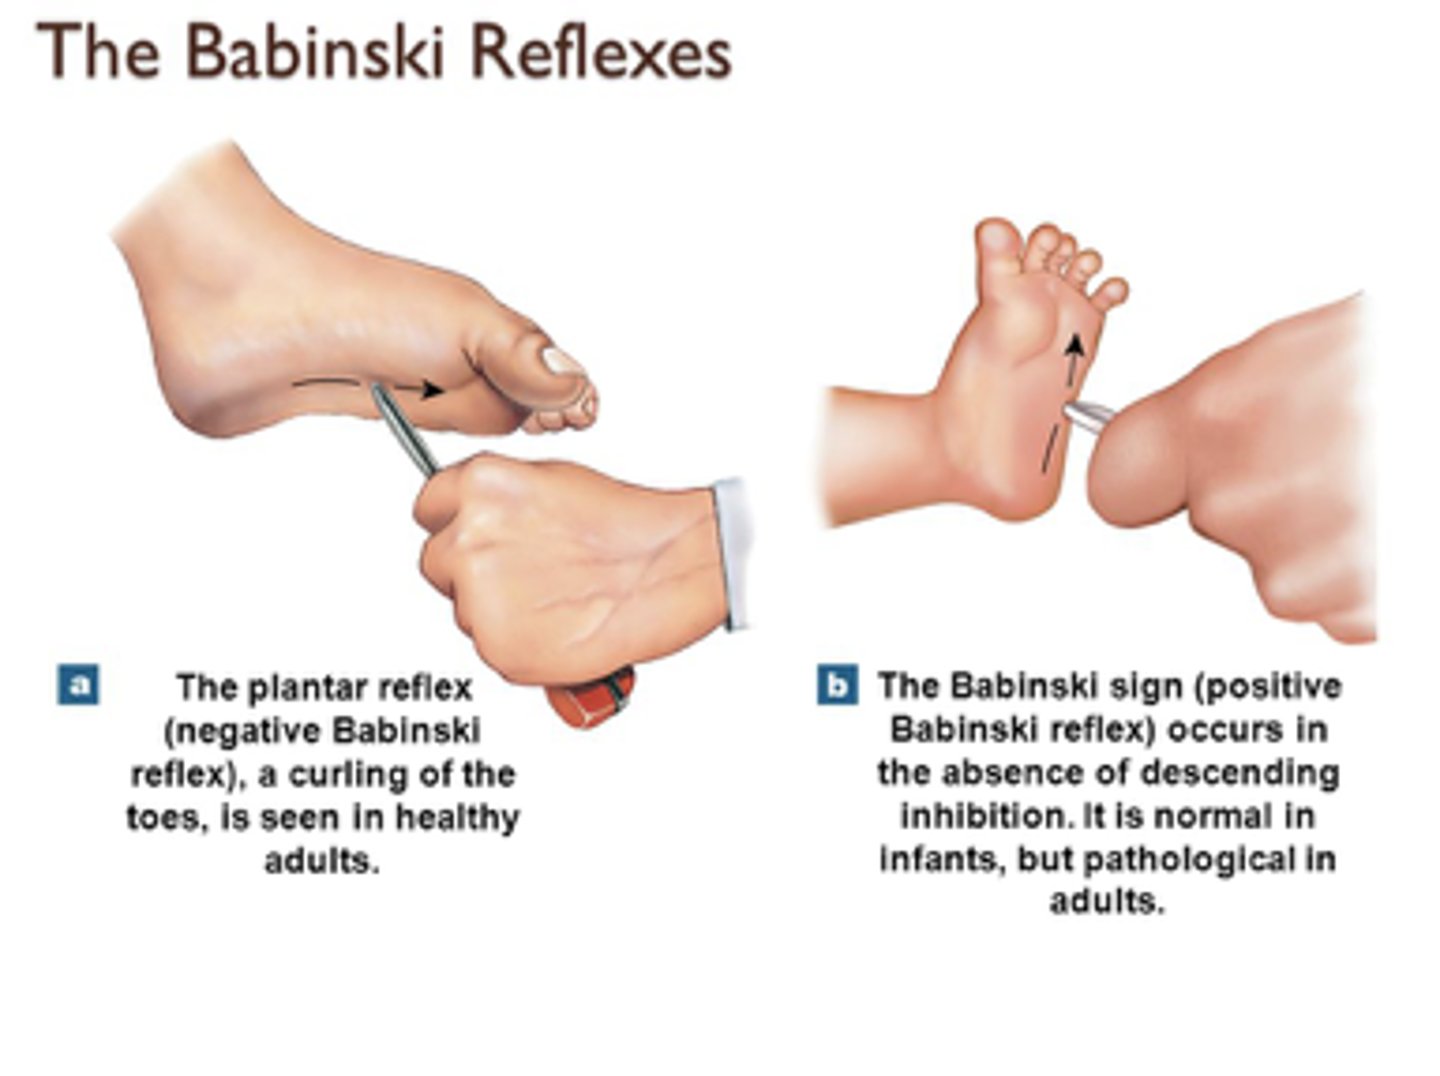

How long is it normal for babinski to be positive (plantar extension) in babies?

birth - 9-10 mo